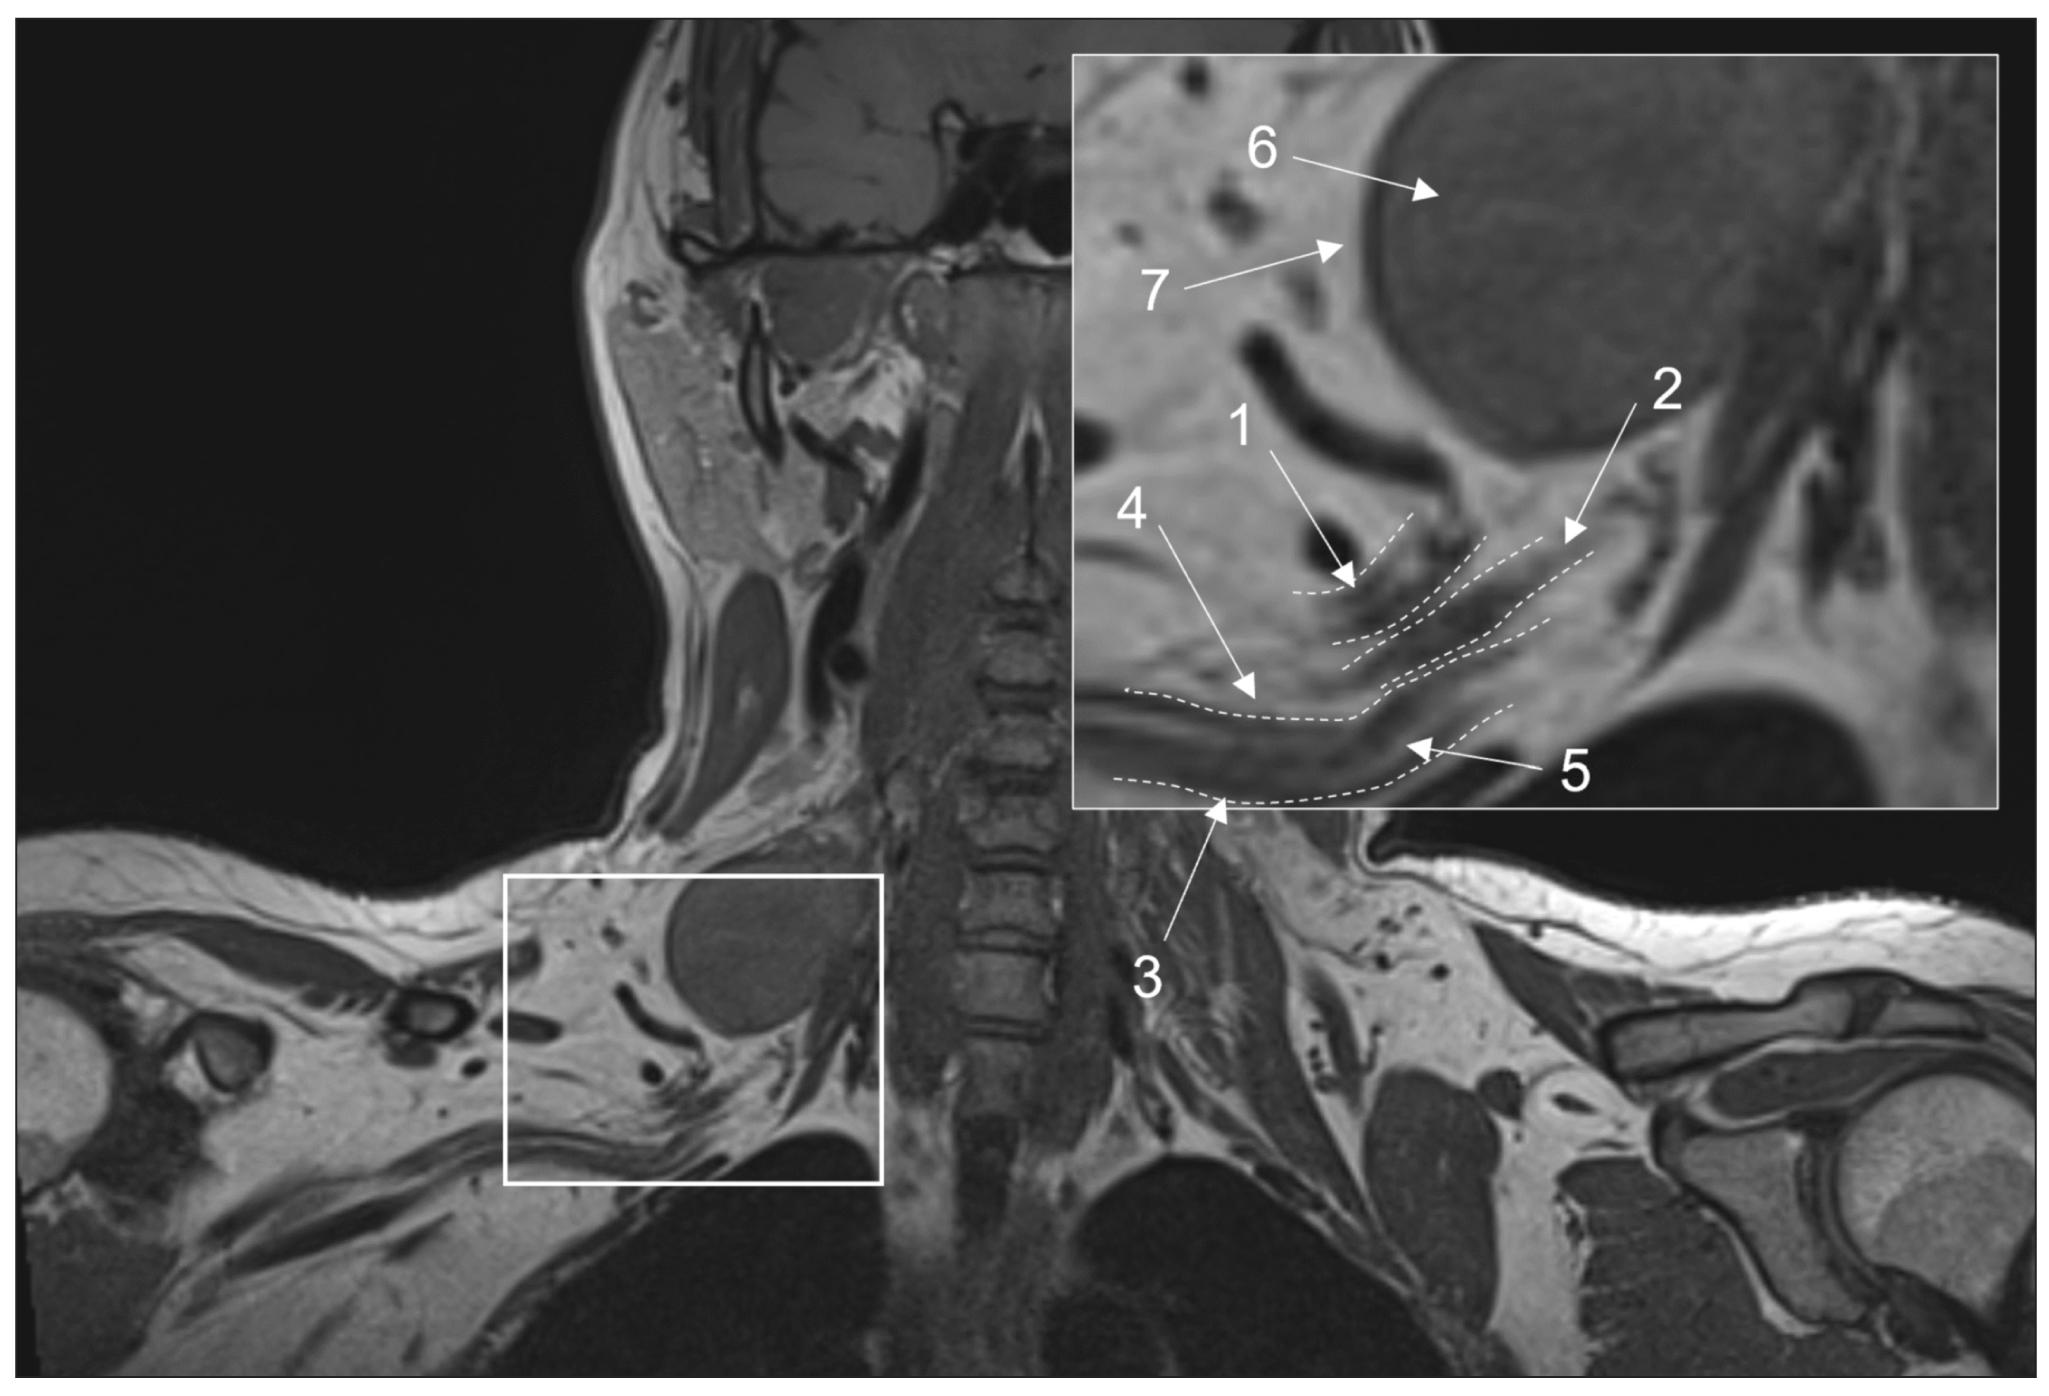

Conventional magnetic resonance imaging of peripheral nerves: MR-neurography

Abstract

Peripheral neuropathy is known to be one of the most common neurological disorders. Despite the great diagnostic value of electroneuromyography and ultrasound, addressing the diagnostics and differential diagnostics of peripheral nerve diseases of different origin could be challenging. In recent years, magnetic resonance tomography has been increasingly used for evaluating cases of suspected or established peripheral neuropathy with excellent results.

This manuscript mainly deals with the advantages and limitations of the aforementioned diagnostic instruments, technical considerations according to different anatomy of peripheral nerves, along with state-of-the-art technical decisions, frequently used magnetic resonance imaging sequences and their diagnostic value based on own observation, and recommendations for contrast enhancement use and different methods of fat suppression.

Currently, there is practically no standardized description of normal magnetic resonance imaging features of peripheral nerves, as well as their changes in different diseases. The evaluation of images is mainly based on the radiologist experience, which obviously decreases method’s diagnostic value. Studies of large numbers involving healthy volunteers and patients with peripheral neuropathies of different origin are required to address this issue.

356-368